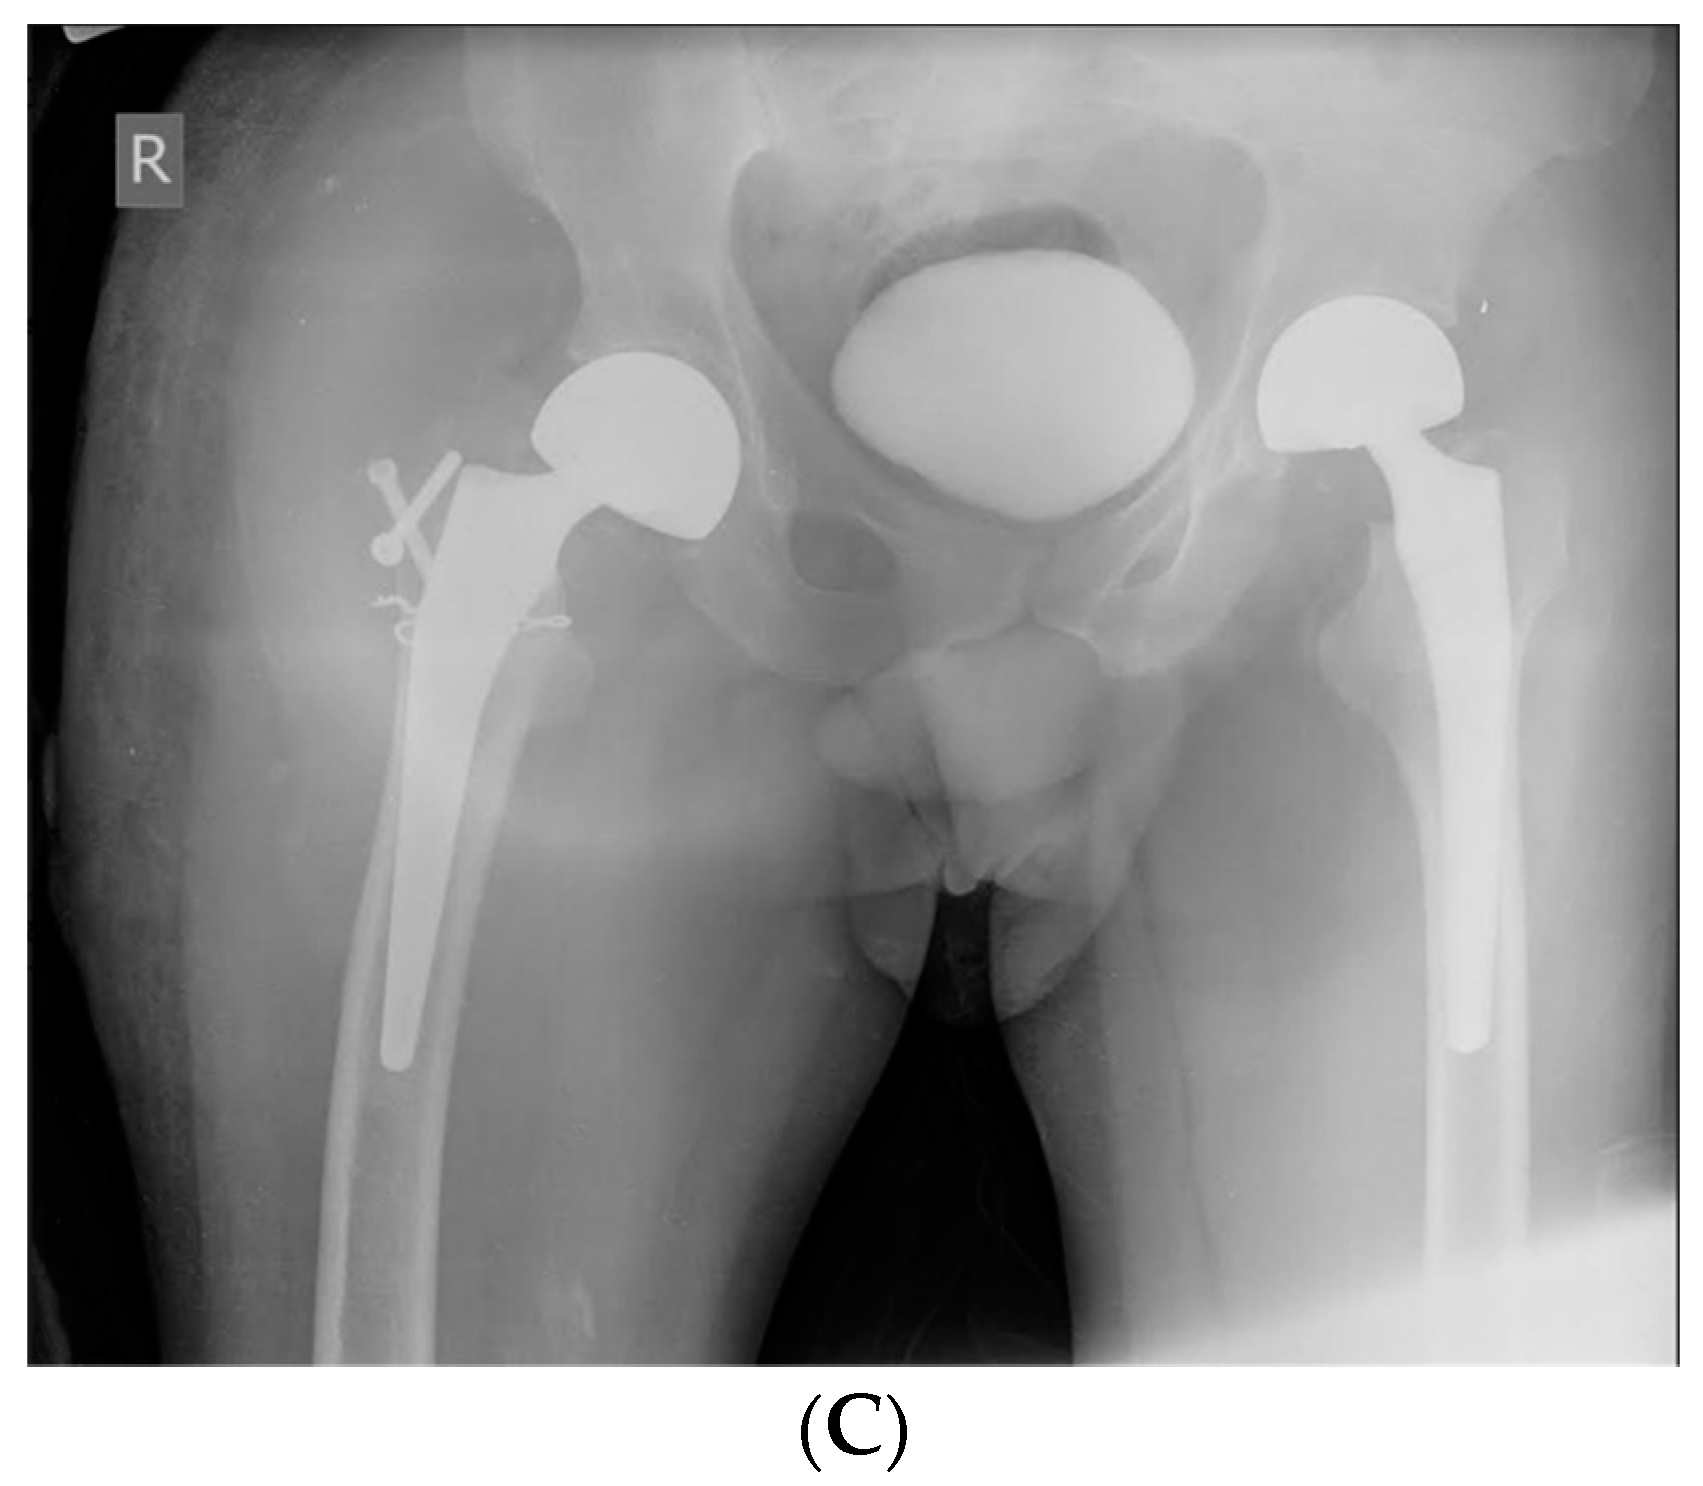

| Case 1. 50-years-old male, with severe haemophilia B | -known and treated for epilepsy -chronic viral hepatitis C | -trauma-related bilateral femoral neck fracture | -bilateral simultaneous hip arthroplasty -the right hip joint is complicated with pertrochanteric fracture, needing an additional osteosynthesis with screws | ~1200 mL (3 units pRBCs) | ~86,856.05 € (91.75% for recombinant FIX concentrate) | No | Good, discharged after 30 days |